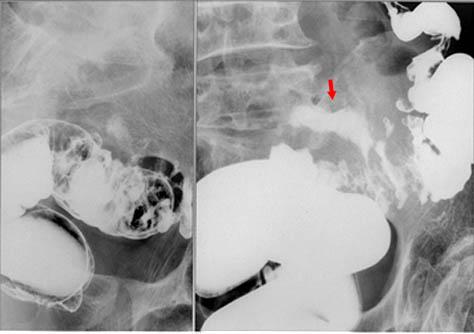

肠憩室周围炎脓肿

乙状结肠憩室周围浓瘤手术病例(东京都台东区浅草消化器研究会病例)

憩室/憩室炎憩室周围浓瘤

部位(按器官分)

大肠/乙状结肠

检查方法

X线